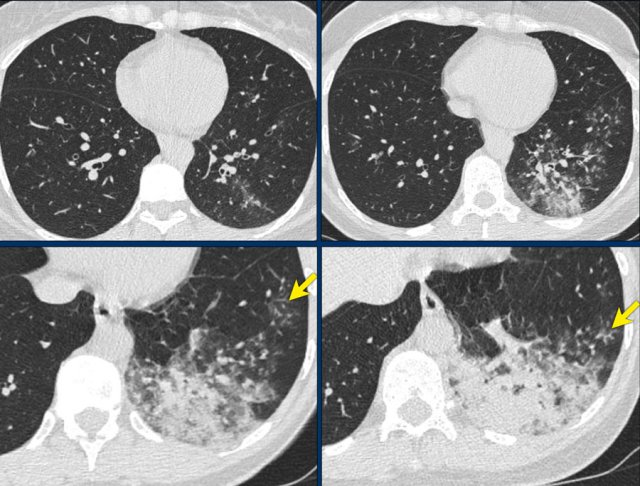

Examples of CO-RADS 3. Click to enlarge. Examples of CO-RADS 3. Click to enlarge.

Case 5

7 day of complaints.

CT: multifocal consolidations with surrounding GGO.

PCR negative.

Case 6

Recent Influenza A . History of pulmonary hypertension.

Started coughing again.

CT: bilateral central consolidations with diffuse GGO.

Re-test: COVID-19 PCR: negative and Influenza A: positive.